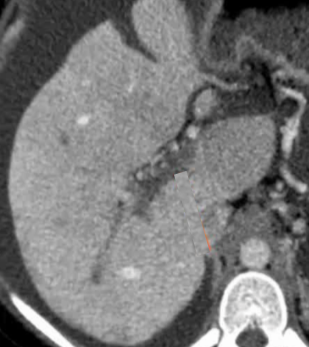

该程序包含以下步骤: 经脾脏入路:在超声引导下,刺穿脾静脉内的一个实质内分支。 在通过脾静脉造影确认了静脉通路后,导管和导丝被推进,以穿过脾静脉并抵达血栓化的门静脉。在门静脉/右门静脉分支处放置圈套器,为TIPS穿刺精准定位。TIPS穿刺圈套器,并穿过圈套器完成TIPS

步骤: 鉴于慢性血栓形成的复杂性: 一种经脾脏途径的门静脉再通术(PVR)。 随后是经颈静脉肝内门体分流术 。

结果:术后影像学检查显示门静脉和脾静脉的血流情况有所改善,且残留血栓极少。